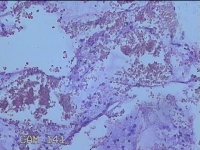

宫颈管内容物

性别

女

年龄

35岁

临床诊断

宫颈上皮内肿瘤?

一般病史

月经干净4天,符合HPV12阳性,TCTASCUS。

标本名称

大体所见

纱布一块,内有灰白暗红色不规则碎组织2.3x1.8x0.3cm一堆。

慢性宫颈炎,伴糜烂。